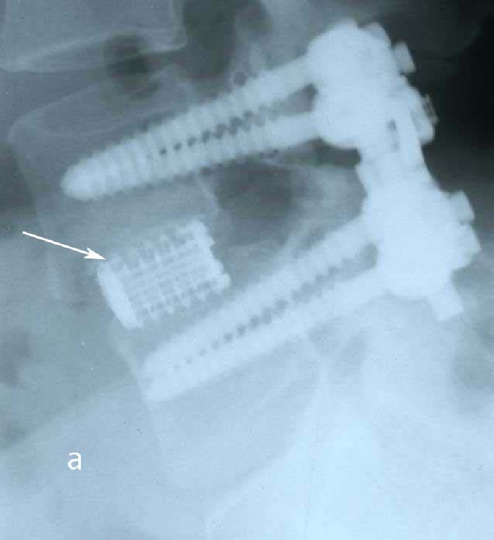

Рис. 2a,b. Рентгенограмма поясничного отдела позвоночника в боковой (а) и прямой (b) проекции после операции транспедикулярной фиксации L4-L5 позвонков. Стрелкой указаны 2 титановых цилиндрических кейджа.

Рис. 6a. Рентгенограмма поясничного отдела позвоночника в боковой (а) и прямой (b) проекции после операции транспедикулярной фиксации L4-L5 позвонков. Стрелкой указаны 2 титановых цилиндрических кейджа. Рис. 6b. Рентгенограмма поясничного отдела позвоночника в боковой (а) и прямой (b) проекции после операции транспедикулярной фиксации L4-L5 позвонков. Стрелкой указаны 2 титановых цилиндрических кейджа.